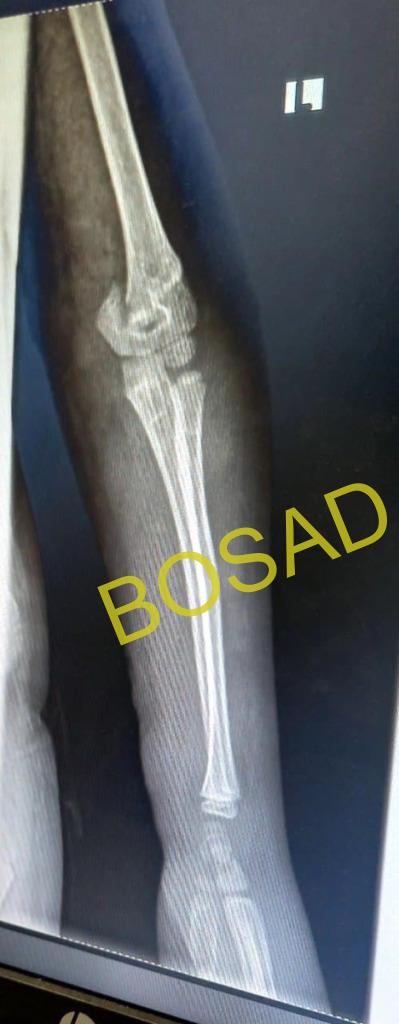

An eight years old male patient came with the complaint of falling down accident from height. He has injured his left elbow area one week ago. For this complaint the family took him to traditional bone setter first, where massaged with Vaseline and tight bamboo splint was applied. When his left upper extremity starts to have blisters and swelling, his family brought him to our facility. On arrival he was stable but he had blisters and septic joint. x-ray and other investigations were performed and diagnosed with left supracondylar fracture plus left elbow septic joint. For this, surgical intervention was done and the infection was managed accordingly. Finally discharged with improvement